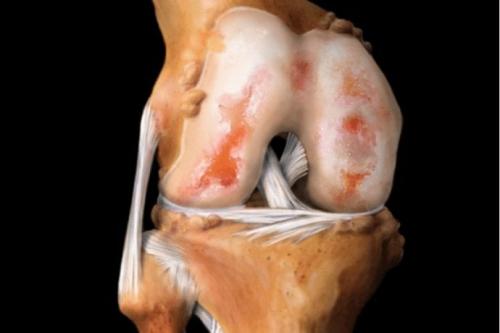

Увлажненный слой хрящевой ткани выстилает все суставные поверхности.

Если хрящ начинает разрушаться, оголяется соседняя костная ткань с грубой шероховатой поверхностью, которая повреждает противоположный хрящ.

В результате происходит дальнейшее нарушение выработки синовиальной жидкости, ведущее к постепенному отмиранию хрящевой ткани и утрате функции сустава.